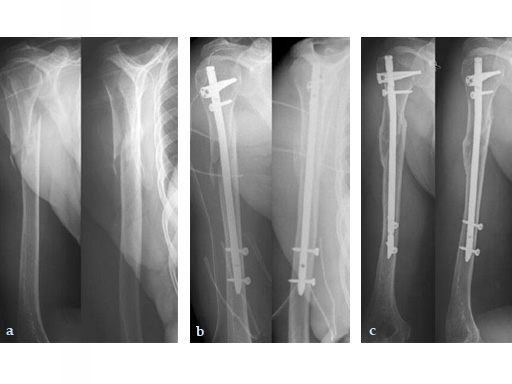

a) A proximal spiral fracture of the humerus shaft with progression into the greater tubercle of humerus following a 74 - year- old womans fall at home. (Preoperative)

b) Treatment with UHN and a Spiral Blade. (Postoperative)

c) X-ray five months after surgery showing healed fracture.